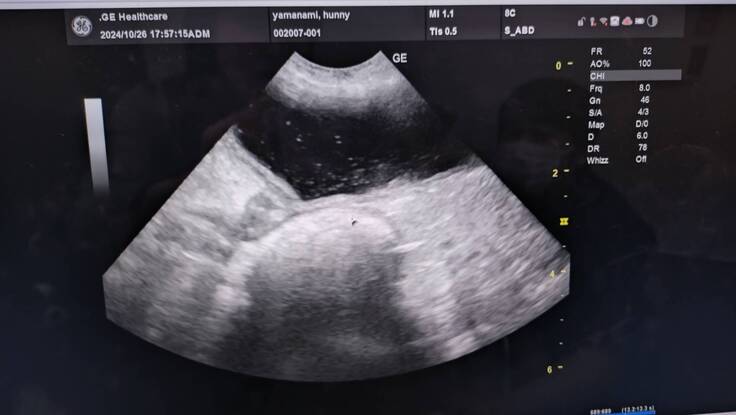

エコー写真→キラキラ白く写っているのが菌、脂肪や結石様のもの浮遊物

腎臓結石あり→悪さはしていない

右、左の腎臓も変形などなし

今のところ腫瘍とかは確認できるものはなさそう